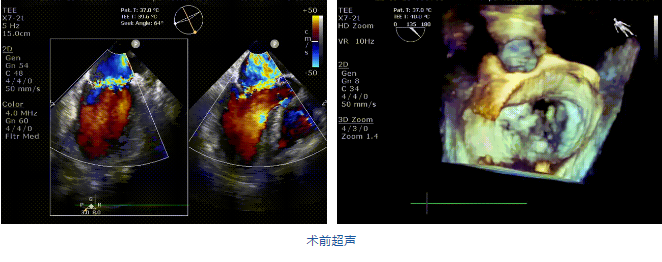

接受治療的是一例二尖瓣重度反流的患者,主訴“突發(fā)間歇性胸悶,氣急6天”。術(shù)前超聲提示:1.二尖瓣脫垂伴重度關(guān)閉不全(瞬時量30ml);2.左心、右房增大(左房容積110ml,左室容積129ml,右房容積55ml);3.左室收縮功能正常?;颊咴诔浞謽?biāo)準(zhǔn)化藥物治療后(GDMT)仍然癥狀明顯,韓林教授及其團隊唐楊烽教授,以及心超科的周廣為醫(yī)生決定使用我國創(chuàng)新器械JensClip為患者進(jìn)行二尖瓣緣對緣修復(fù)手術(shù)。

在阜外醫(yī)院潘湘斌教授團隊的支持下,手術(shù)經(jīng)股靜脈-房間隔入路,采用全身麻醉插管,在TEE和DSA引導(dǎo)下完成房間隔穿刺。置入JensClip瓣膜夾系統(tǒng)后,在左房調(diào)整瓣膜夾的位置和軸向,后進(jìn)入左室,在TEE引導(dǎo)下捕捉二尖瓣前后瓣葉,并關(guān)閉瓣膜夾。經(jīng)TEE反復(fù)確認(rèn)手術(shù)效果后最終鎖定并釋放瓣膜夾。術(shù)后即刻超聲顯示瓣膜夾位置穩(wěn)定,功能良好,二尖瓣反流由術(shù)前4+減少至微量,手術(shù)圓滿成功。